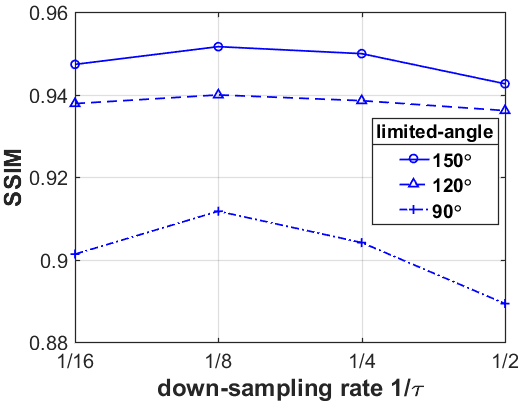

What is more, as shown in Table III, IV and V, the smaller the down-sampling rate, the better the reconstruction result. Since the quality of the image prior decreases as the resolution decreases for the limited-angle reconstruction problems, there is a trade-off between the resolution and the quality. Thus, we track the relationship between the resolution of the low-resolution image priors and the performance of our LRIP-net. As shown in Fig. 9, the best reconstruction results are obtained using the low-resolution image prior with down-sampling rate . Although the smaller the condition number of the system matrix, the better the numerical stability of the solution, it does not mean that the better the performance of our LRIP-net.